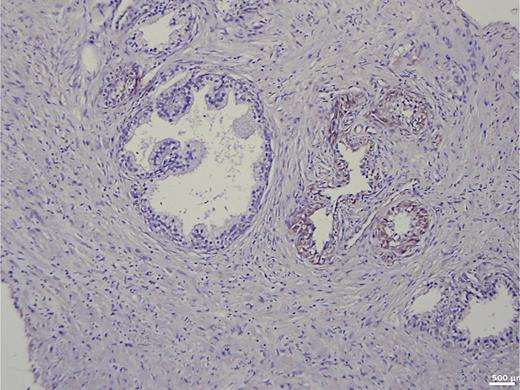

In the group of patients without carcinoma, the vast majority exhibited BSP expression of less than 1%. Twenty-nine out of thirty patients had a value below 5% (Table 1). One patient showed a BSP expression of 9%; however, the expression was observed only in basal cells in a condition of basal cell hyperplasia combined with chronic inflammation (Fig. 1). BSP expression in prostate tissue without carcinoma and without basal cell hyperplasia is shown in Figure 2.